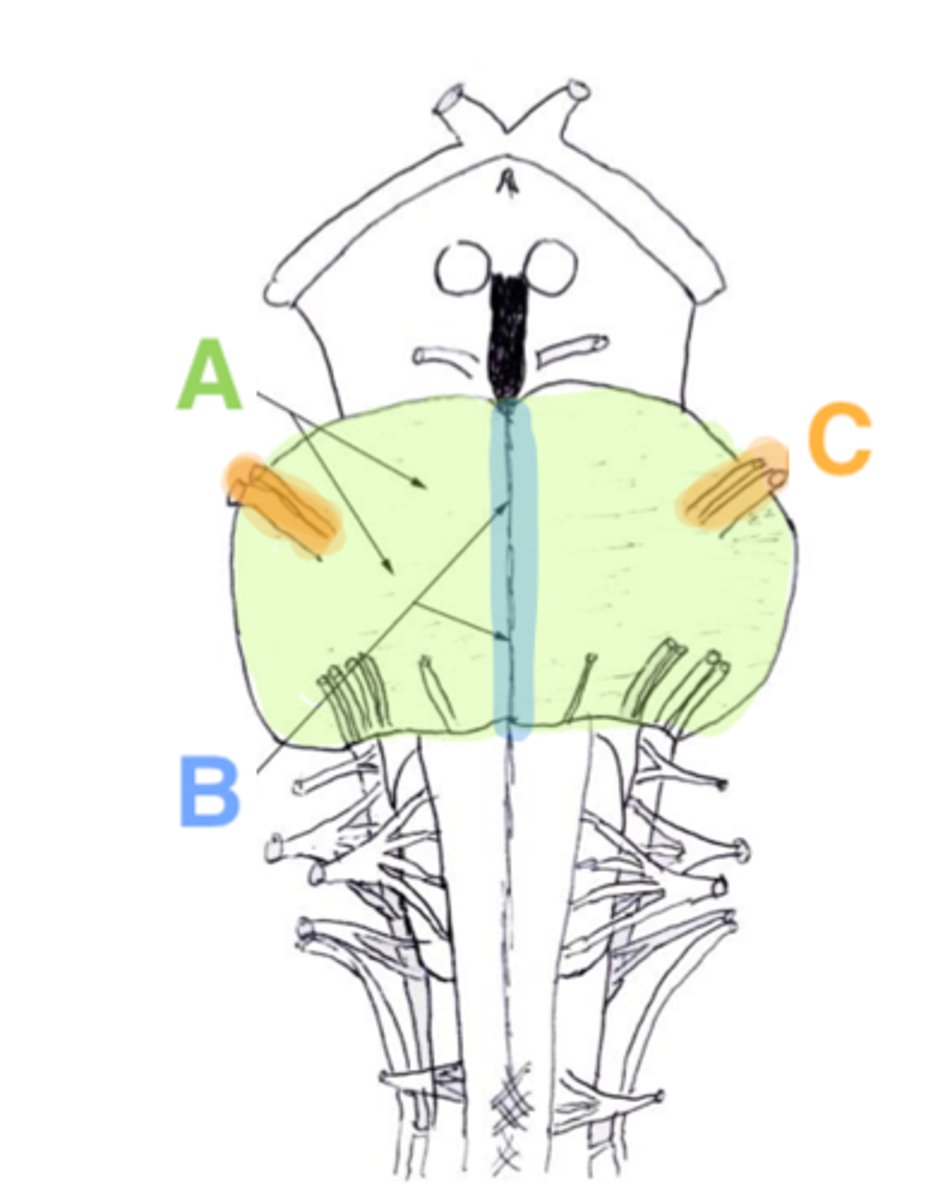

refers to the large round protuberance on the ventral pons that represents a "bridge" of horizontally oriented fibers connecting the right and left sides

basilar portion

longitudinal midline groove of the pons that is the superior continuation of the ventral median sulcus/fissure, containing a namesake artery

basilar sulcus

white matter stalks that connect the pons to the cerebellum

middle cerebellar peduncles

What is the only cranial nerve that attaches to the pons?

CN V

portion of the pons that is dorsal to the basilar portion and represents mostly longitudinally oriented fibers and cranial nerve nuclei

**also helps to form the floor of the 4th ventricle

tegmentum

A

basilar portion

B

basilar sulcus

C

CN V

B

middle cerebellar peduncles

tegmentum